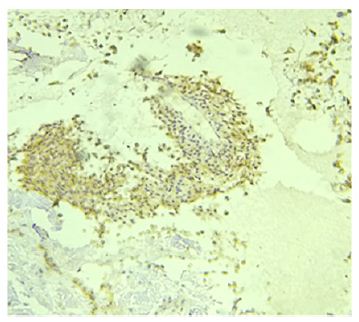

On the distal part of the incision further dissection was done and recurrent branch of radial artery was ligated (Figure 5) to avoid injury to it. Bicepital tuberosity on radius was identified and bed prepared (Figure 6). An anchor screw was passed into it and with the fibre wire, tendon was re attached (Figure 7), as we expected there was enormous tension on tendon and hence a long arm slab in 1100 of flexion and supination was given. Patient was discharged on second post op day and at one month follow up slab and sutures were removed, elbow mobilisation started (Figure 8). Wound was healed well and at 2 months post of he had near normal range of movement and without any pain and quick DASH score improved to 11 at 2 months post op and it is improving further.